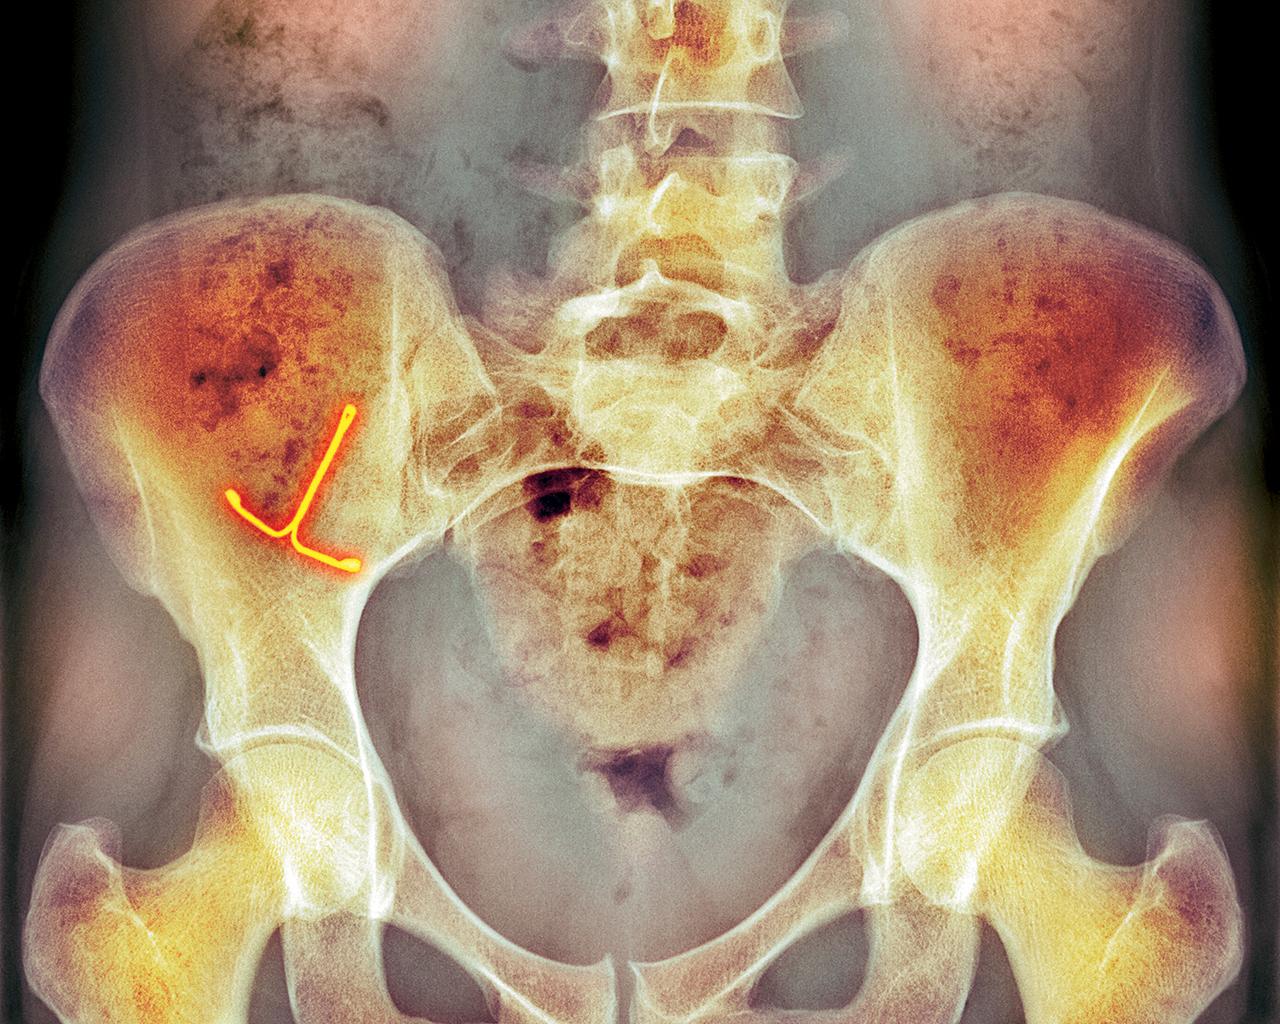

- Частичное выпадение или смещение контрацептива, что может быть видно при УЗИ или рентгенологическом исследовании малого таза.

Субъективные признаки смещения препарата могут проявляться следующим образом: ощущение спирали в области внутреннего и наружного зева цервикального канала или влагалища, а также изменение длины нитей, которые были предварительно закреплены. При полном выдавливании нити не могут быть ощутимы при пальпации, а спираль не обнаруживается при зондировании, ультразвуковом и рентгенологическом исследовании малого таза.